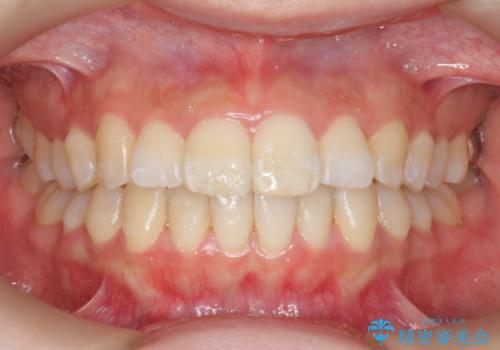

インビザラインで出っ歯の治療

- 「目立つ前歯の出っ歯をなんとかしてほしい。」と矯正治療を希望され来院されました。

突出した上顎の前歯に加え、ガタつきの目立つ下顎の歯列も同時にマウスピース矯正インビザラインで整えていきます。

突出間(所謂 出っ歯)のある前歯の位置は大幅に改善され、審美性が大きく向上しました。

加えて奥歯も噛み合わせも良くなったことで、咬合状態が安定しより安定した歯列を獲得することができました。